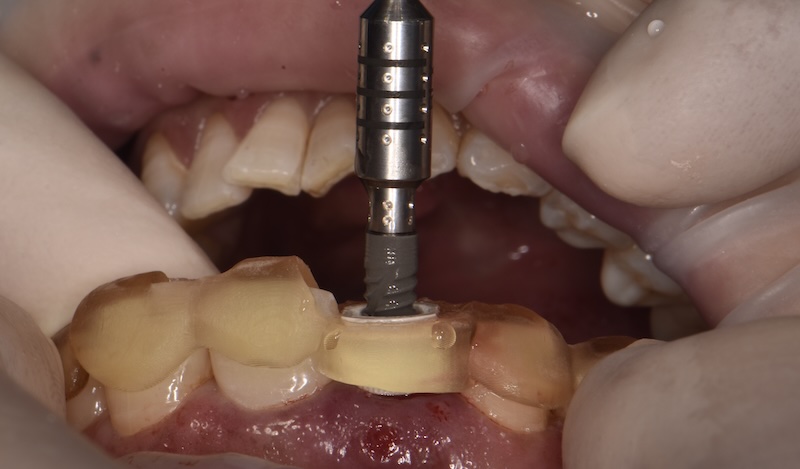

Surgical guide

The planned position is translated into a precision guide that directs placement during surgery.

No estimation — the thinking is done beforehand.